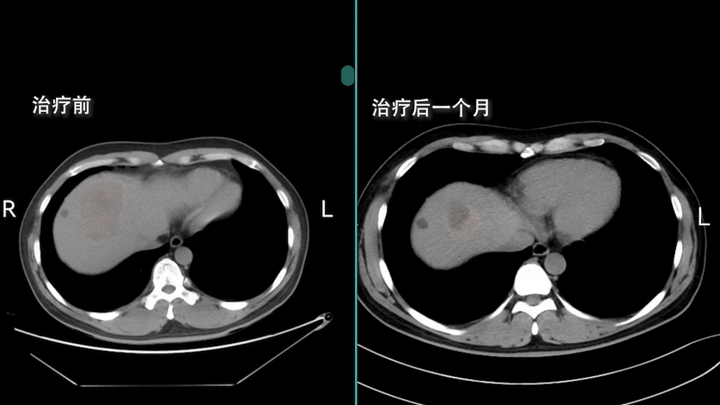

▎“靶向+免疫+中药”,他从“只剩 3 个月”到肝部肿瘤全消!

53岁的明叔(化名),带着表弟和邻居,坐了十几小时硬座从湖北来到北京。这条路他两年没走了,但无比熟悉——2年前,他被诊断为弥漫性肝癌晚期,癌肿大如鸭蛋,并被当地医院断言生命仅剩3个月。

绝望中,明叔找到了钟伟主任。在“靶向+免疫+中药”的治疗方案下,奇迹悄然发生。服药10天,明叔腹部的胀痛开始减轻;1个月后复查,肿瘤缩小了1cm多;4个月后再检,肿瘤缩至2cm多。到2021年底,肝部肿瘤全部消失。